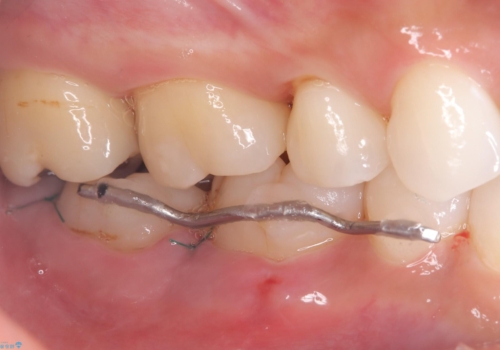

来院時、右下7遠心9mm、舌側6mmと深い歯周ポケットを認めました。

遠心から舌側、唇側に及ぶ深い垂直的骨欠損も認めたため、歯科衛生士による歯周基本治療の後、歯周外科(再生療法)を行いました。

レントゲン写真は、処置後一年経過時のもので、歯周ポケットは遠心4mm、舌側3mmまで減少、出血なし。

一度目の再生療法でできる骨形態は移行的でないこともあるため、経過を診つつ骨整形も必要であれば今後行う予定です。